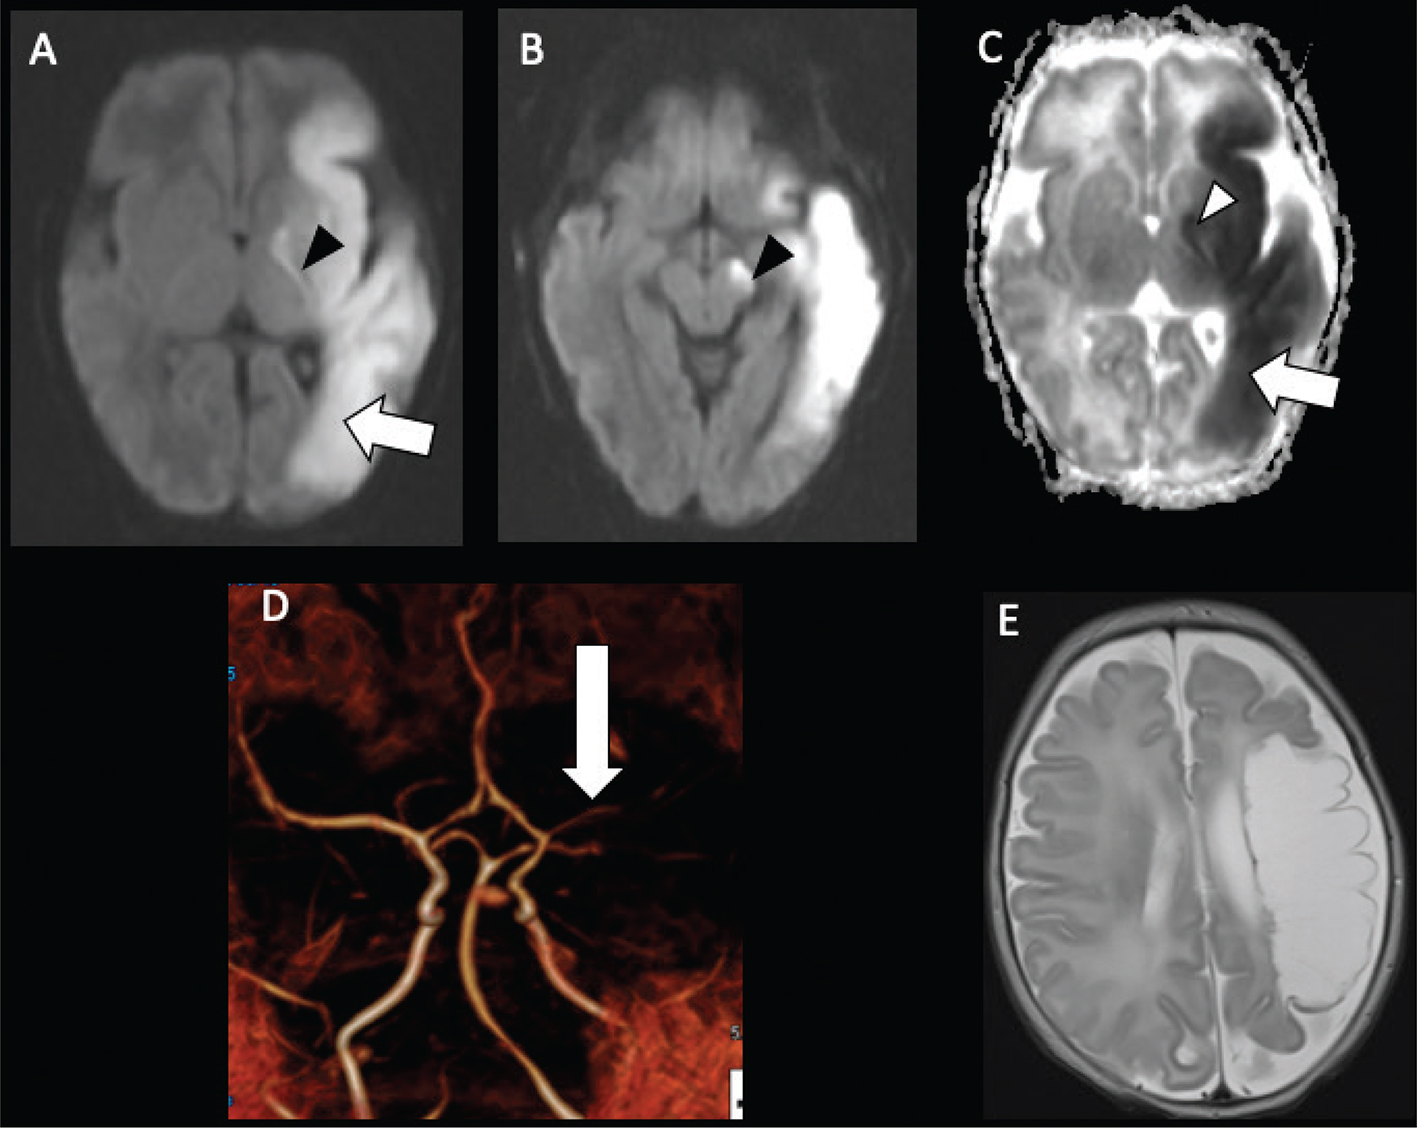

On MRI, acute infarcts demonstrate reduced diffusivity within minutes, exhibiting high signal on DWI and low computed diffusivity on ADC maps (Figure 5) (46). Diffusivity remains reduced for about 6 days, peaking at about 3 days, before pseudonormalization occurs, with diffusivity then increasing to above normal by the second week (4750). Timing of DWI changes can be affected by the age of the patient, size of the stroke, and how quickly collateral blood flow is recruited. DWI also detects early or pre-wallerian degeneration in infants (also referred to as “acute network injury”), characterized by injury to the antegrade white matter tracts following acute infarct and manifests as reduced diffusivity in white matter pathways affected by the infarction within a few days of the injury (Figure 5) (51). Common pathways affected by acute network injury include the corpus callosum, thalamus, and descending corticospinal tract. When seen along the corticospinal tracts, acute network injury is highly predictive of poor motor outcomes (52, 53).

Fig 5

Figure 5. Acute neonatal arterial ischemic infarction in a three-day-old girl with seizures. Axial DWI (A) and (B), and axial ADC (C) images show extensive area of reduced diffusion in the left MCA territory (arrows). Arrowheads (A, B, C) indicate pre-Wallerian degeneration in the posterior limb of the internal capsule and left cerebral peduncle along the corticospinal tract. D. 3D time-of-flight MRA shows abrupt absence of flow in the left MCA (arrow). Axial T2-weighted image (E) at 5-month follow-up shows extensive encephalomalacia and volume loss in the left MCA territory. Case courtesy of Dr. Tamara Feygin, Department of Radiology, Children’s Hospital of Philadelphia.